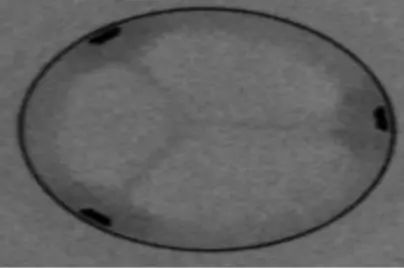

术中食道超声确认满意后释放血管塞

复查造影

跨瓣压差下降为20左右,超声复查微量瓣周漏,瓣膜植入位置良好,遂闭合入路送回病房,一周后康复出院。